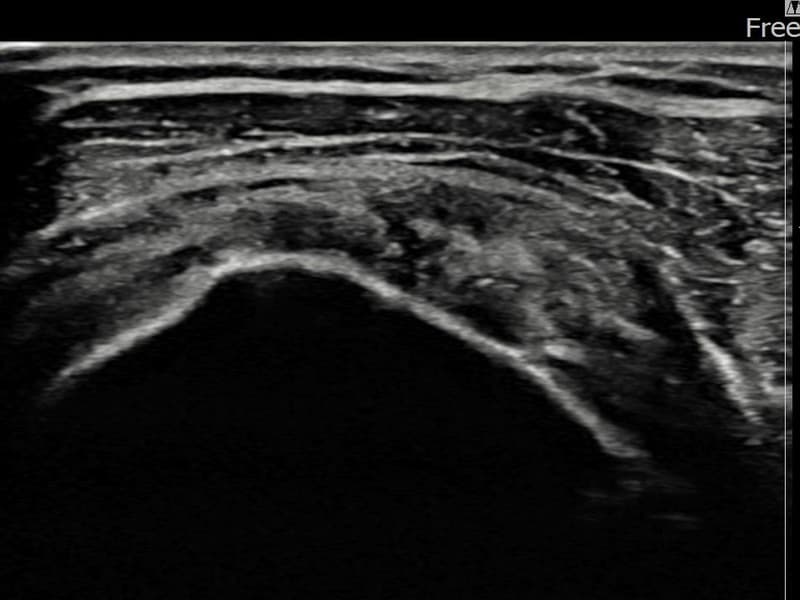

施術後

術前超音波にて左 棘上筋腱 関節面側部分断裂・左肩棘上筋腱のエコー不連続と腱欠損(3.5mm × 3.1mm (부분파열))を確認。術後超音波では断裂部位が再生組織で充填され、腱の連続性回復とエコーパターンの正常化が確認されました。

持続する左肩痛で来院された患者様です。超音波検査にて左 棘上筋腱 関節面側部分断裂(欠損:3.5mm × 3.1mm (부분파열))を確認し、超音波ガイド下で非手術的縫縮術を施行しました。術後は約4〜6週間のブレース装着の後、段階的なリハビリプログラムを実施。経過超音波で腱の連続性回復を確認し、患者様は無事に日常生活へ復帰されました。